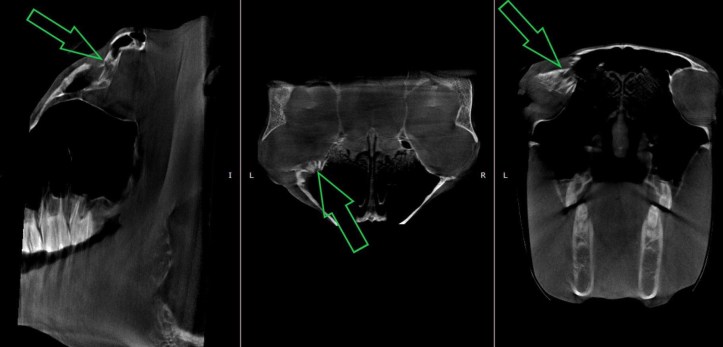

A year ago today I decided to TLC Caz. He’s an old 24 year old Black Tobiano gelding at Webb. He’s a former 3* Dressage mount and the sweetest goober when he lets you in. He has been through a lot in life, he was kicked in the eye before I started working at Webb; and his eye has a resulting pocket from fracturing the orbital. (Pictured Below) I got him that Lavender Mint plaid flymask to help with eye build up.